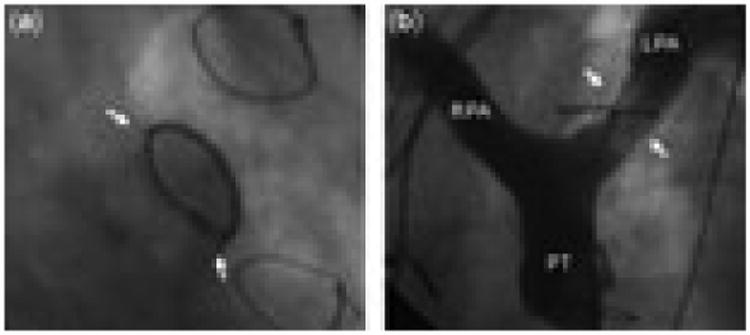

Figure 3.

(a) A central left pulmonary arterial stent in this patient with transposition who underwent repair with an arterial switch operation and anterior translocation of the pulmonary arteries is fractured along two axial planes (arrows), anteroinferior and posterosuperior, and severely compressed. (b) A pulmonary angiogram with cranial angulation demonstrates severe obstruction across the fractured and compressed stent, with obvious thinning of the contrast column within the stent, indicating a narrow anteroposterior vessel diameter. LPA, left pulmonary artery; PT, pulmonary trunk; RPA, right pulmonary artery.

In our experience, in situ fracture of stents used to treat central pulmonary arterial stenosis is relatively common. Although the design of our study does not allow a true estimate of the incidence of fracture, or of time to failure of the initial stent, we found that, of pulmonary arterial stents evaluated by catheterization at least 3 years after placement, one-fifth were fractured. Pulmonary arterial stents implanted in environments exposed to large cyclic external compressive forces appear to be particularly susceptible to fracture. Stents juxtaposed to the ascending aorta, most often in the central right pulmonary artery, posterior to the ascending aorta, had the highest risk of fracture. Larger stents, both in length and deployed diameter, were also more prone to fracture, which may speak to environmental effects resulting in an increased likelihood of compression, or to stent-related factors such as size- dependent differences in biomechanics. Patient-related factors associated with higher risk of fracture included a diagnosis of common arterial trunk or transposition after an arterial switch operation, and the presence of a right aortic arch. These factors are most likely important because of their association with increased risk of pulmonary arterial compression. For example, the space between the ascending and proximal descending aorta may be relatively small when the aortic arch is right-sided, or in patients with a particularly large aortic root or ascending aorta, as is often seen in association with common arterial trunk (Fig. 1), which may increase the likelihood of compression of the right pulmonary artery. Similarly, after the arterial switch operation with the Lecompte manoeuvre, the branches of the pulmonary trunk may be draped around, and consequently subject to compression by, the ascending aorta (Fig. 3). In fact, 4 of the 11 fractured stents in the central left pulmonary artery in this series were in patients who had undergone an arterial switch operation. Other circumstances in which stents in the left pulmonary artery fractured were in patients with tetralogy of Fallot, in whom the angle of origin of the left pulmonary artery from the pulmonary trunk is abnormally acute and prone to kinking, and in patients with functionally univentricular disease who had undergone reconstruction of the aortic pathway, and subsequently developed compression and stenosis of the central left pulmonary artery by the large neo-ascending aorta anteriorly (Fig. 2).

The manifestations of fracture may vary considerably. The effect of fracture and compression on luminal size and haemodynamic obstruction is a function both of the relief of stenosis from angioplasty and stenting in the first place, and the cross-sectional area of the lumen. When exposed to very high or complex multiaxial compressive forces, a fractured stent may collapse almost completely, or fracture along multiple planes, resulting in a vascular cross-section that takes a lenticular shape (Fig. 1). Severe eccentricity was observed in one-fifth of fractured stents, and in three-tenths of cases there was severe obstruction of the stented pulmonary arterial segment (Fig. 3). On the other hand, most of the fractures identified were associated with modest collapse and mild obstruction. In some of these cases, the compressive forces acting on the stent may be such that very little deformation of the cross-sectional geometry occurs once the point of plastic deformation has been reached, and in others, the fractured edges of the stent overlap, with the contour of the separate segments remaining more or less intact, resulting in a relatively circular cross-sectional area, only with a smaller diameter (Figs. 2 and 4).